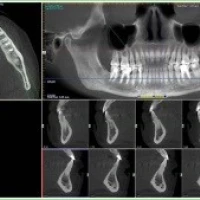

Семинар по радиодиагностике в стоматологии